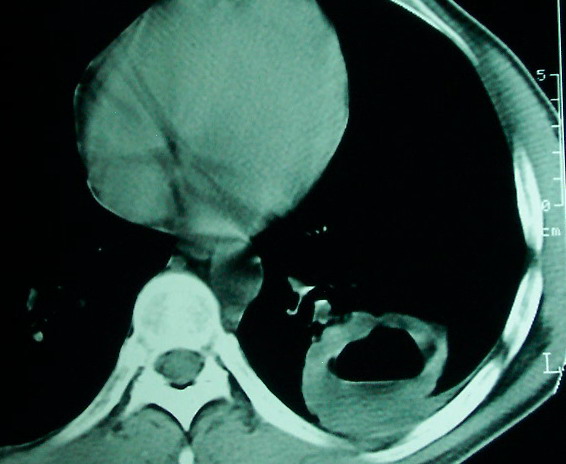

m      37y      发热   咳脓痰月余      ct肺脓肿但住院抗炎治疗后双肺内结节不知该如何解释

治疗后见左肺下野病灶较前缩小但双肺内结节影似无变化请较各位老师该如何下结论    治疗前wbc14.5 治疗后wbc 11.0

左下肺病灶除了明显的厚壁空洞 气液平外,明显见壁结节,另两肺多发小结节,综合考虑:左下肺周围性肺癌伴肺内转移.

鳞癌肺肺转移:厚壁空洞,洞壁厚薄不均,内似有壁结节,肺脓肿临床有无提示,血像如何?病灶周围很干净,没有明显渗出,很勉强?

如果你仔细的同层面对比,你会发现所有的病灶均有比较明显的吸收、缩小。病变的形态,特别是脓肿的形态、壁的厚薄、内壁均有很大的变化,均在往好的方面发展。与临床症状、血像均符合,治疗效果比较显著,就是肺脓肿并双肺的化脓性炎症灶。